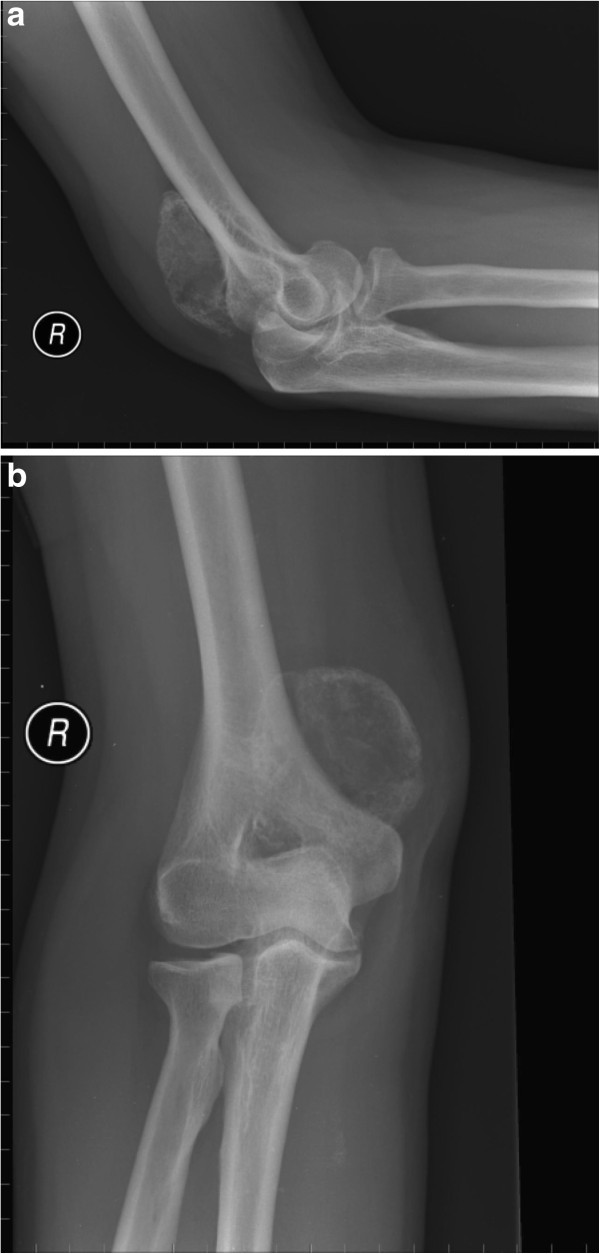

From www.researchgate.net

Elbow synovial chondromatosis. Preoperative radiology showed (a)... Download Scientific Diagram Synovial Osteochondroma Elbow the elbow is the most affected joint in the upper limbs. the definitive diagnosis of synovial chondromatosis of the elbow joint requires a comprehensive medical history,. 2 because the dominant elbow is more commonly. osteochondromas are benign chondrogenic lesions derived from aberrant cartilage from the perichondral ring that. synovial chondromatosis (also called synovial osteochondromatosis) is a. Synovial Osteochondroma Elbow.